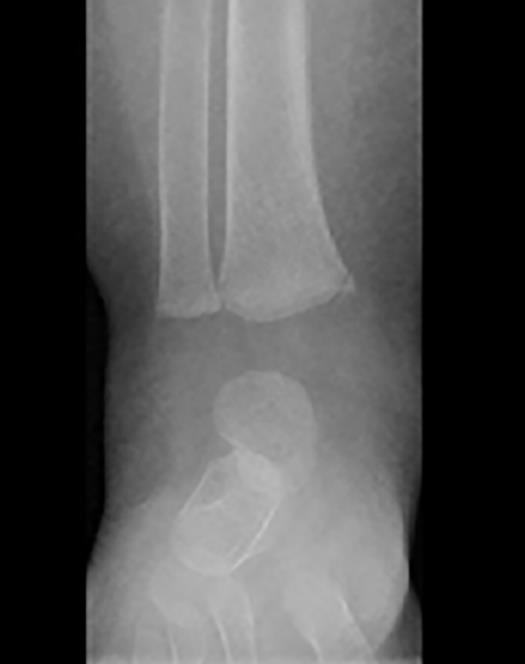

A 12-year-old boy has been brought to the emergency department with an ankle injury sustained during a football game. After a tackle he was unable to weight bear on his right foot and he noticed that his ankle was painful and swollen.

His x-ray is shown below.

What is the correct diagnosis?

A. Epiphyseal injury of the distal fibula (Salter-Harris I)

B. Epiphyseal injury of the distal tibia (Salter-Harris I)

C. Epiphyseal injury of the distal tibia (Salter-Harris II)

D. Epiphyseal injury of the distal tibia (Salter-HarrisIII)

E. Disruption of the distal tibio-fibular joint

D. Epiphyseal injury of the distal tibia (Salter Harris III)